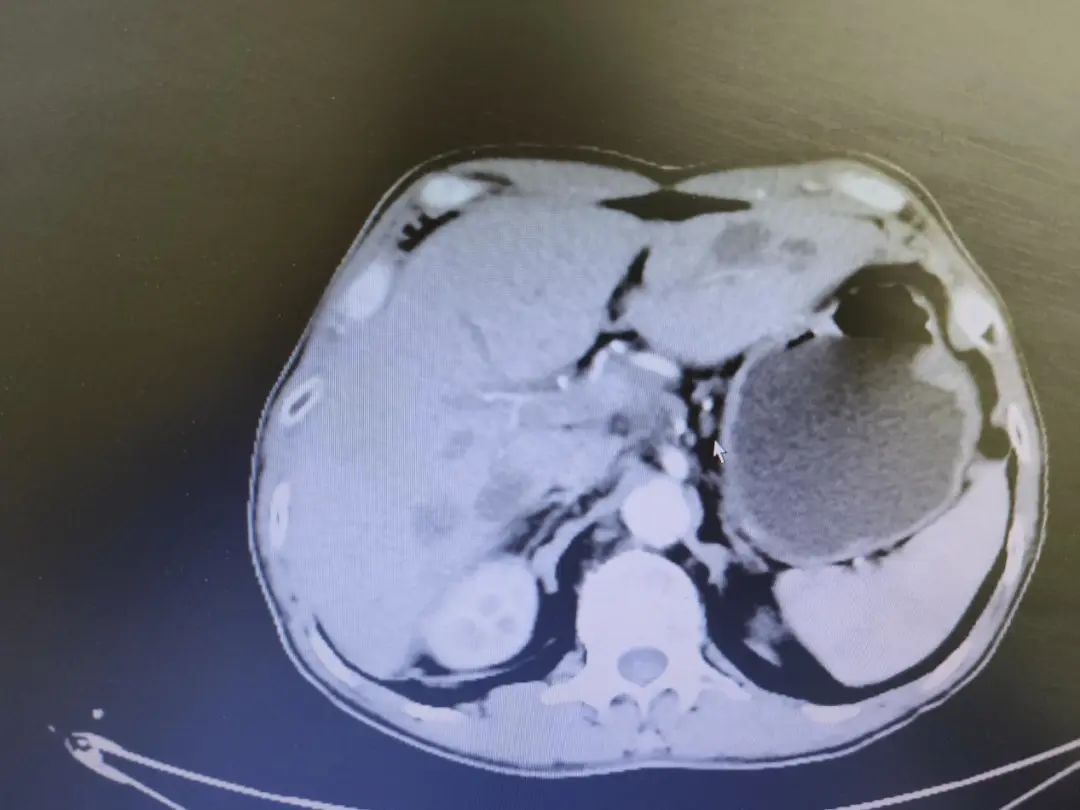

我院6周期化疗后影像(2022年6月27日)